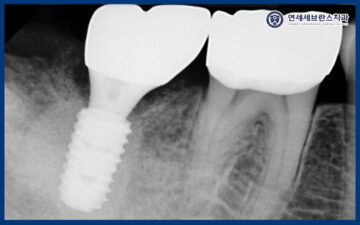

25.01.07

임플란트는 초기 고정력이

무엇보다 중요한 치료이기 때문에,

식립 후 한 달 뒤 내원하셨을 때

다시 촬영을 통해

상태를 확인하였습니다.

촬영 결과를 바탕으로

고정이 잘 이루어지고 있는지,

주변 치조골과 잇몸의 회복 상태를

세심하게 평가하였습니다.